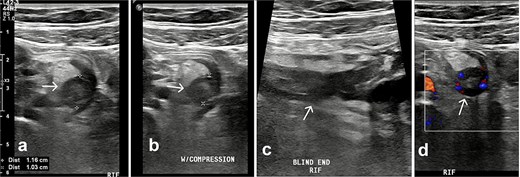

A contrast-enhanced CT confirmed a thickened, inflamed appendix (12 mm diameter) with periappendiceal fat stranding and minimal pelvic fluid (Fig. 2).

CT axial plane demonstrated a thickened appendix (white arrow) in the right iliac fossa measuring 12 mm.